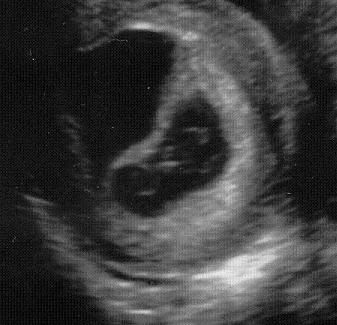

6,6mm-es petezsákom van, benne szikhólyag ábrázolódik. :) Jövőhéten megint UH.

Csöpke- ha én tegnap ennyit láttam volna babócából, akkor nagyon boldog lennék!!! Biztos jó a méret ne aggódj! Melyik kórházban voltál? Jövő héten én is megyek hétfőn, remélem én is látok már "ilyet"!

Te nem ilyesmit láttál tegnap?

Hát én egyre jobban el vagyok keseredve ezzel a 6,6mm-es petezsákkal. :? 13-án volt az első poz tesztem, akkor voltam a pé utáni 10. napon...szóval a legkésőbbi időpont a megtermékenyülésre szeptember 3, vagy 4. Vagyis most 5 vagy 5+1 vagyok. Ahhoz nagyon határeset ez a 7 milis zsák. Bár a szikhólyag látszik, ez jó jel lehet, és volt olyan oldal, ahol azt írták még elfogadható... de azért az 'átlagnak' ahogy olvasom 10-12 mili volt ilyenkor a petezsák. A fiammal 11 volt 2 éve. Hát, majd meglátjuk, bocs ha hosszú voltam. :oops:

Ollem, íme:

ez az UH szept. 12én készült.. úgy 7-8 hetesen..

Mary - Itt az én 8 hetes UH képem:

ja, és itt a petezsák 25,9 mm volt,

a babuci meg 9,6 mm :)